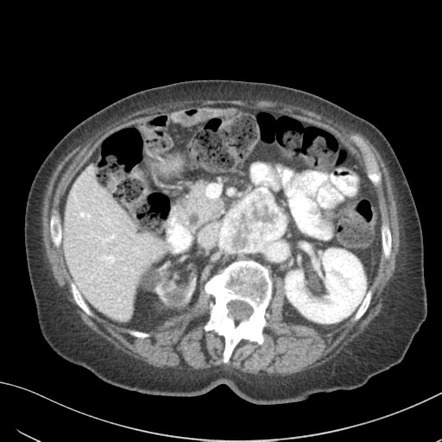

at what HU can an adrenal adenoma be diagnosed?

<10 HU

what % of adenomas are lipid rich?

80%

for adrenal washout protocol, what is diagnostic of an adrenal adenoma? (absolute washout)

> 60% absolute washout

for the adrenal washout protocl what % washout diagnostic for an adrenal adenoma? (relative washout)

> 40% relative washout

relative washout means no noncontrast due to radiation exposure